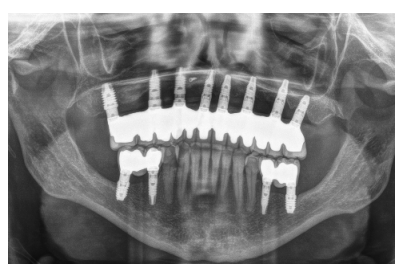

Para iniciar la fase de diagnóstico se realiza una radiografía panorámica que nos de una idea del estado general de ambos maxilares para iniciar el plan de tratamiento. En ella se ve como existe aparentemente altura en el reborde maxilar tanto a nivel anterior como posterior y un nervio dentario bajo en la mandíbula que nos permite tener una mayor cresta ósea residual disponible para la inserción de los implantes (Figura 3).